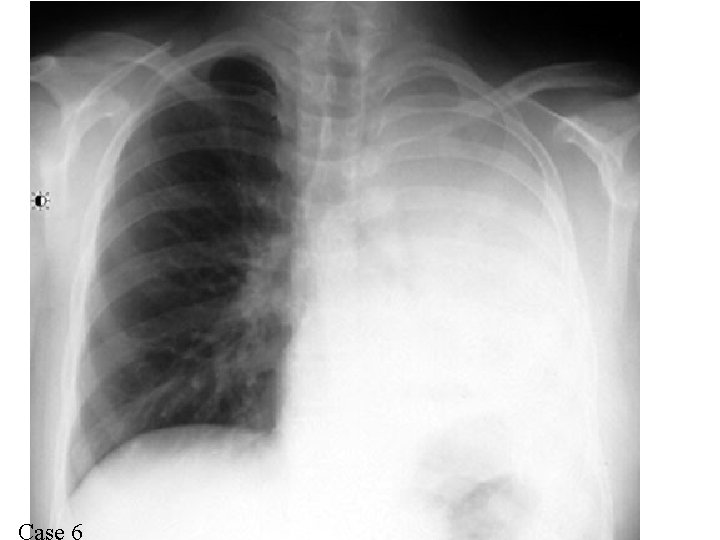

Homogenous Costophrenic angle Meniscus Pleural effusion